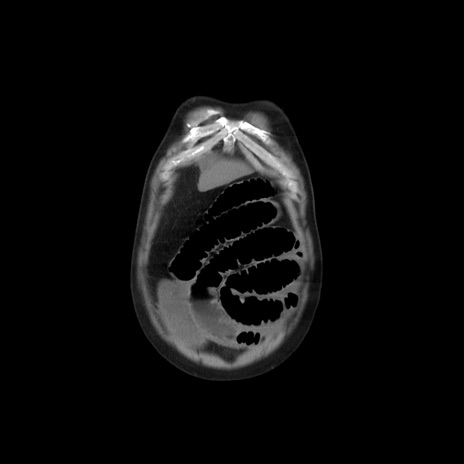

横断像